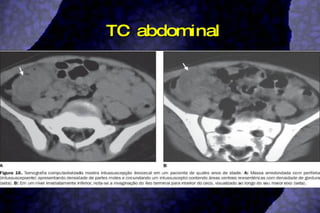

TC abdominal

Diagnóstico História clínicae exame físico; Raios X simples de abdome (massa com densidade de partes moles, distensão de delgado; sinal do alvo, sinal do menisco); Clister opaco (sinal do menisco, sinal da mola espiralada); USG abdominal (sinal do alvo/rosquinha, sinal do pseudo-rim, sinal dos anéis concêntricos múltiplos, sinal do crescente, sinal do sanduíche, sinal do garfo); TC abdominal;